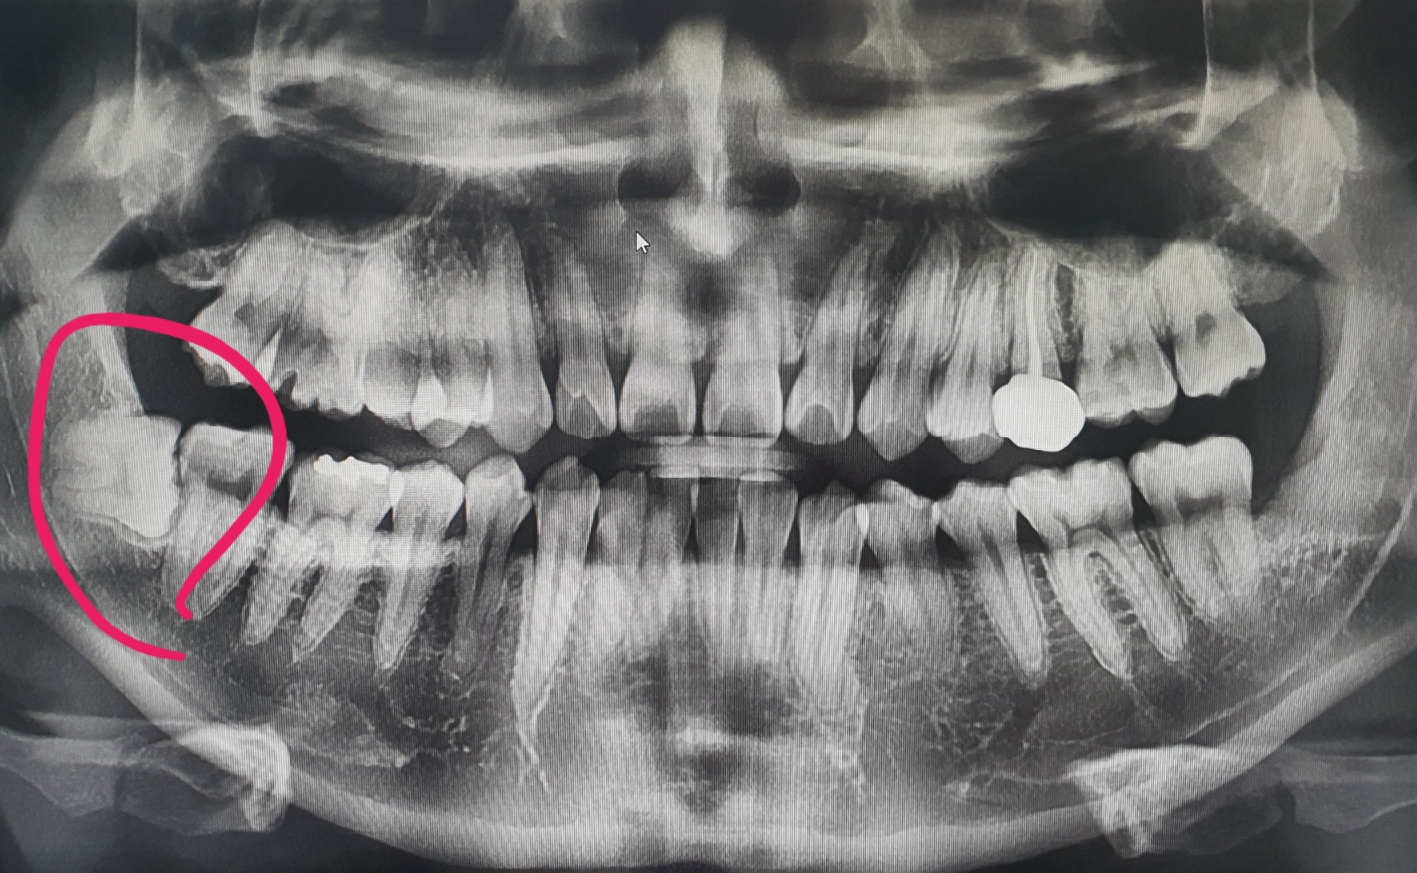

스케일링과 구강검진을 위해 치과에서 엑스레이를 찍었을 때,

양쪽 아래 사랑니가 누워있는 매복사랑니라는 것을 알게 되었습니다.

이 경우 정상 치아의 옆면에 충치가 생길 위험이 매우 높아지기 때문에

최대한 빠르게 뽑아야겠다고 생각했습니다.